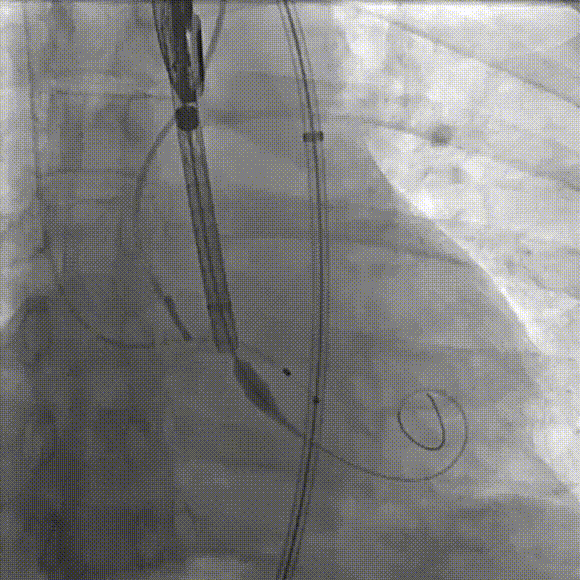

手术过程

在右股动脉穿刺建立通路后,顺利送入大鞘,经食道超声及血管造影确认路径稳定,将ProStyle A®AV32号瓣膜精准释放于目标位置(瓣下2mm),超声显示无瓣周漏,平均跨瓣压差11mmHg,心功能明显改善,患者生命体征平稳。